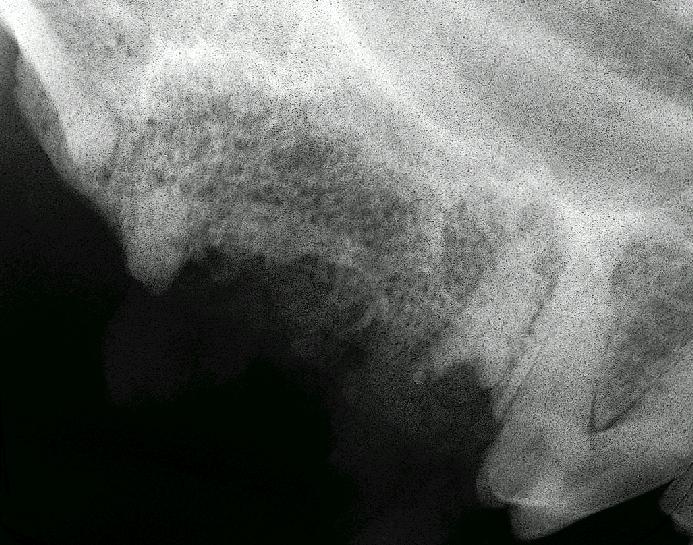

Retained root tip from extracted upper premolar 4